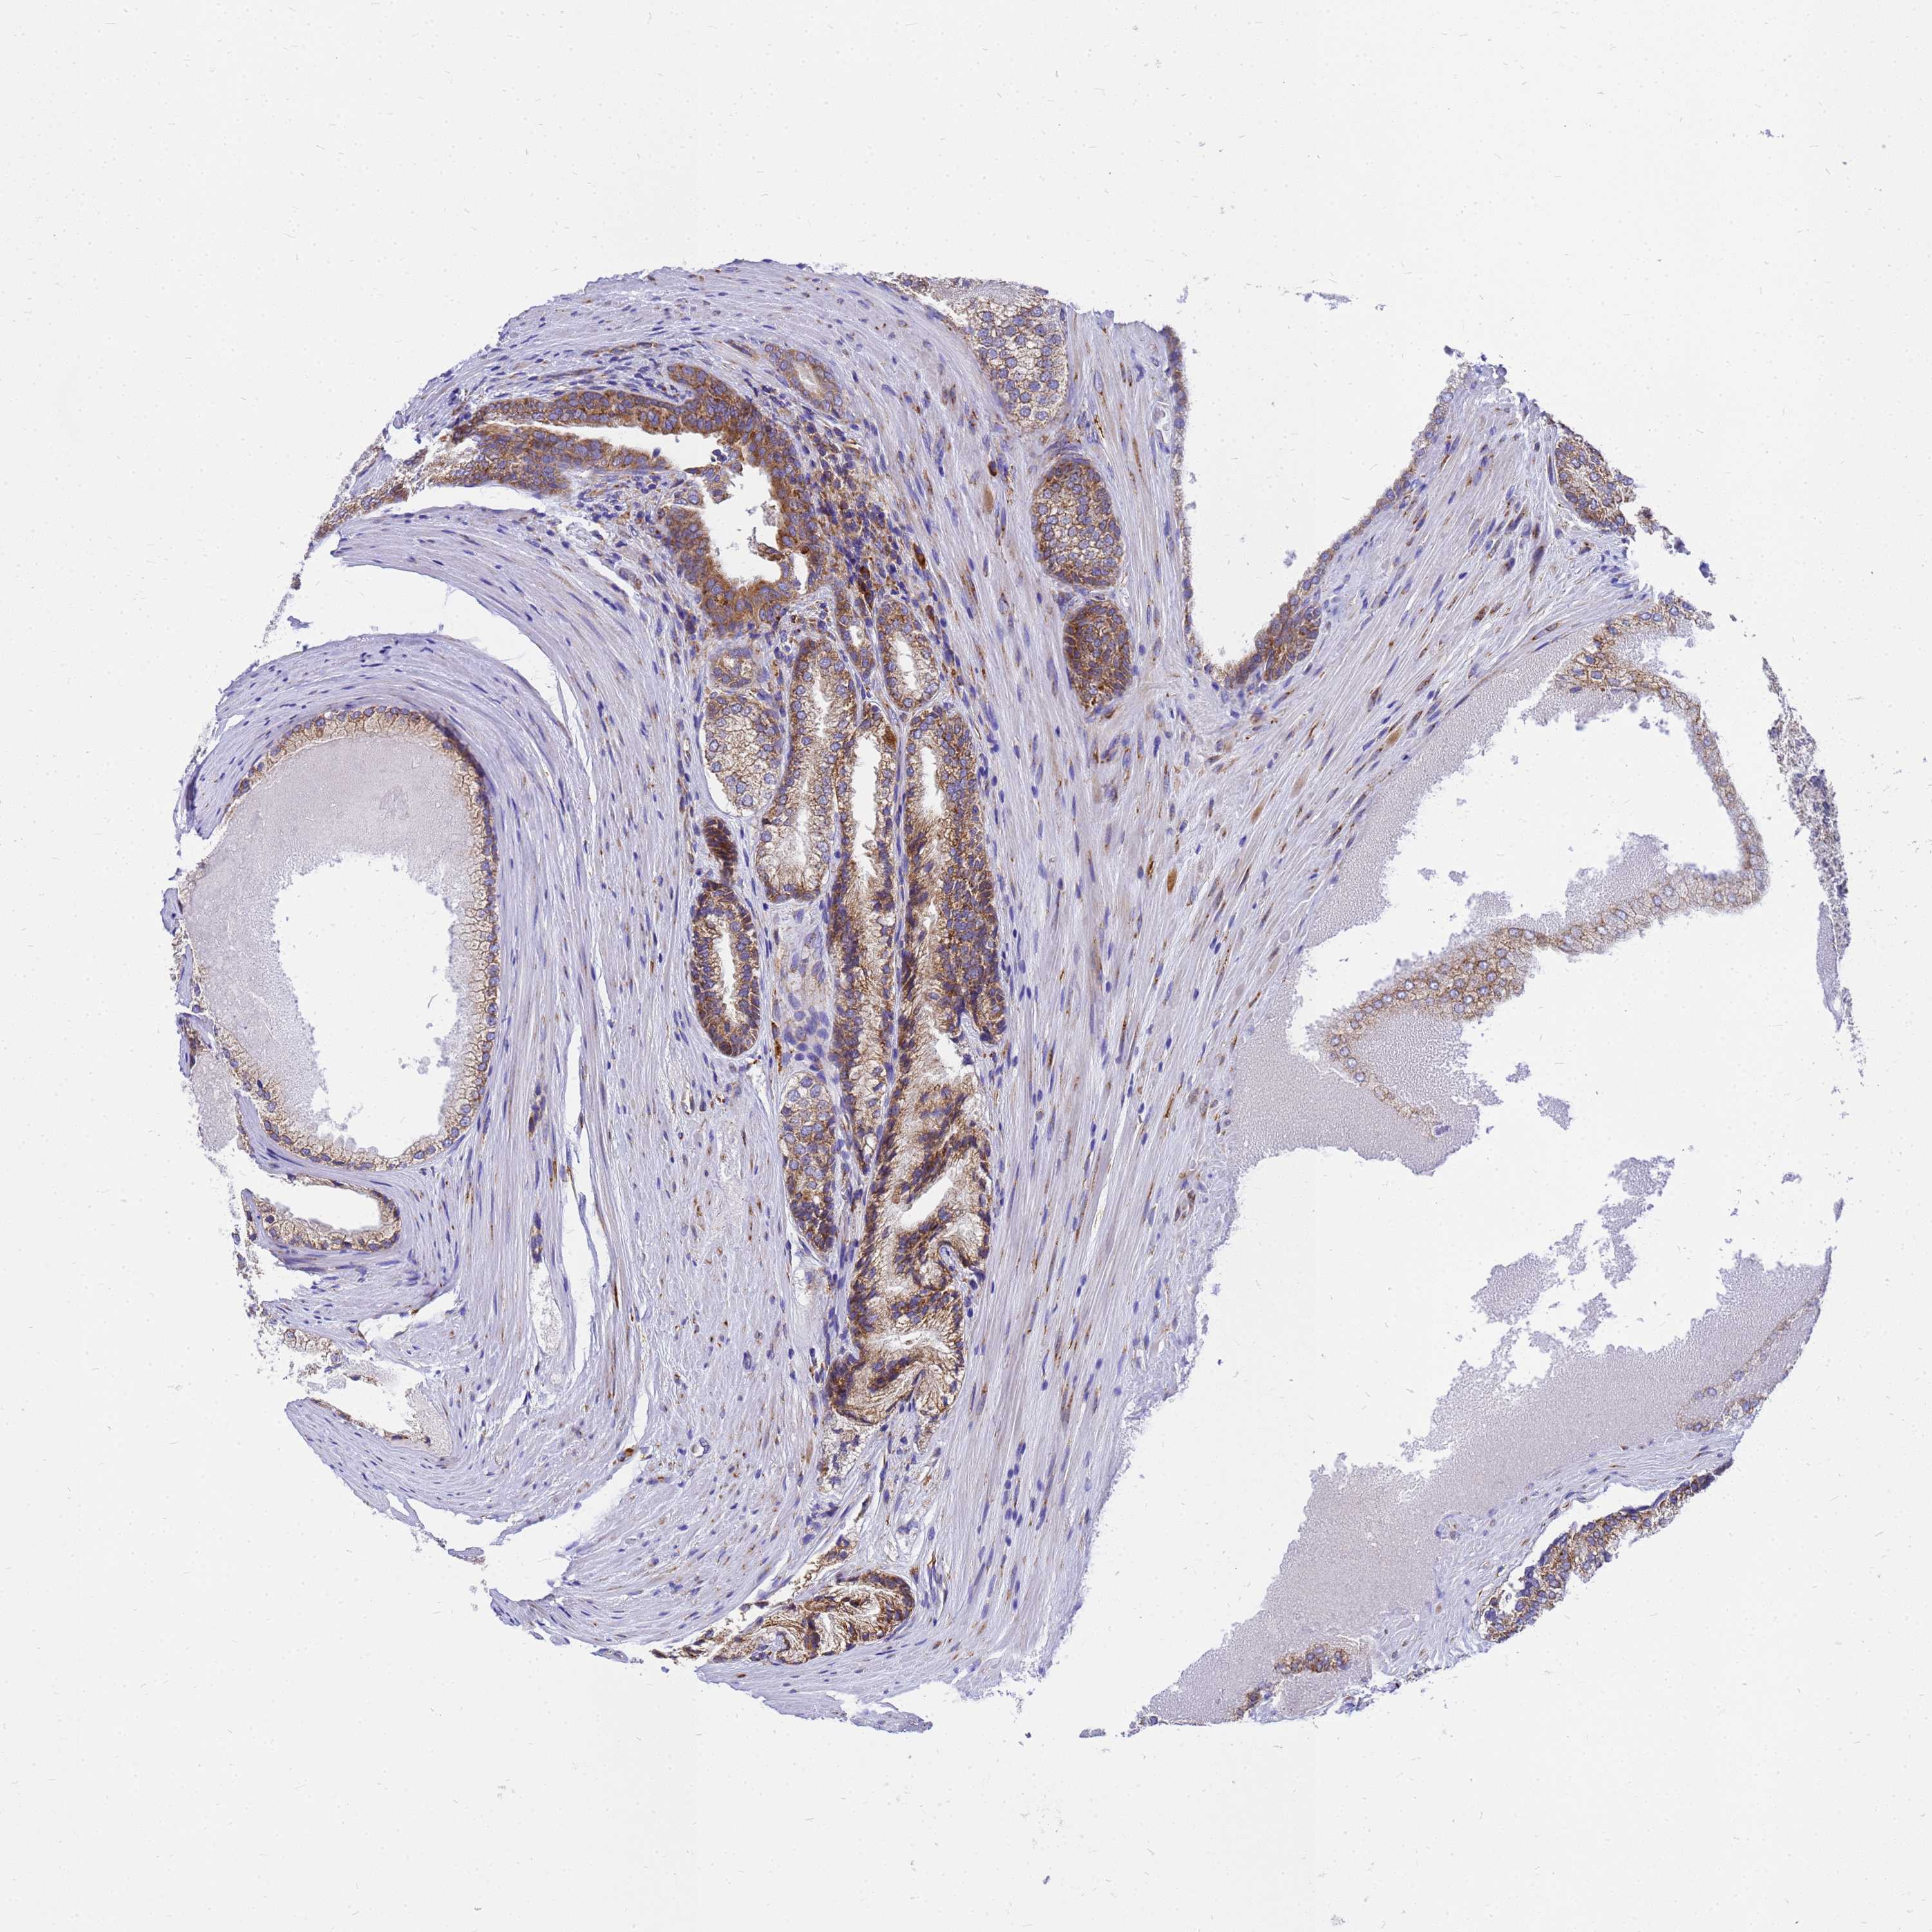

PROSTATE CANCER - Protein expressioni

A mouse-over function shows sample information and annotation data. Click on an image to view it in a full screen mode. Samples can be filtered based on level of antibody staining by selecting one or several of the following categories: high, medium, low and not detected. The assay and annotation is described here.

Note that samples used for immunohistochemistry by the Human Protein Atlas do not correspond to samples in the TCGA dataset.

Antibody stainingi

Antibody staining in the annotated cell types in the current human tissue is reported as not detected, low, medium, or high, based on conventional immunohistochemistry profiling in selected tissues. This score is based on the combination of the staining intensity and fraction of stained cells.

Each image is clickable and will lead to virtual microscopy that enables deeper exploration of all samples and also displays staining intensity scores, fraction scores and subcellular localization as well as patient and tissue information for each sample.

Antibody HPA045101

Staining

High

Medium

Low

Not detected

Intensity

Strong

Moderate

Weak

Negative

Quantity

>75%

75%-25%

<25%

None

Location

Nuclear

Cytoplasmic/membranous

Cytoplasmic/membranous,nuclear

Adenocarcinoma, NOS

Adenocarcinoma, High grade

Adenocarcinoma, Low grade